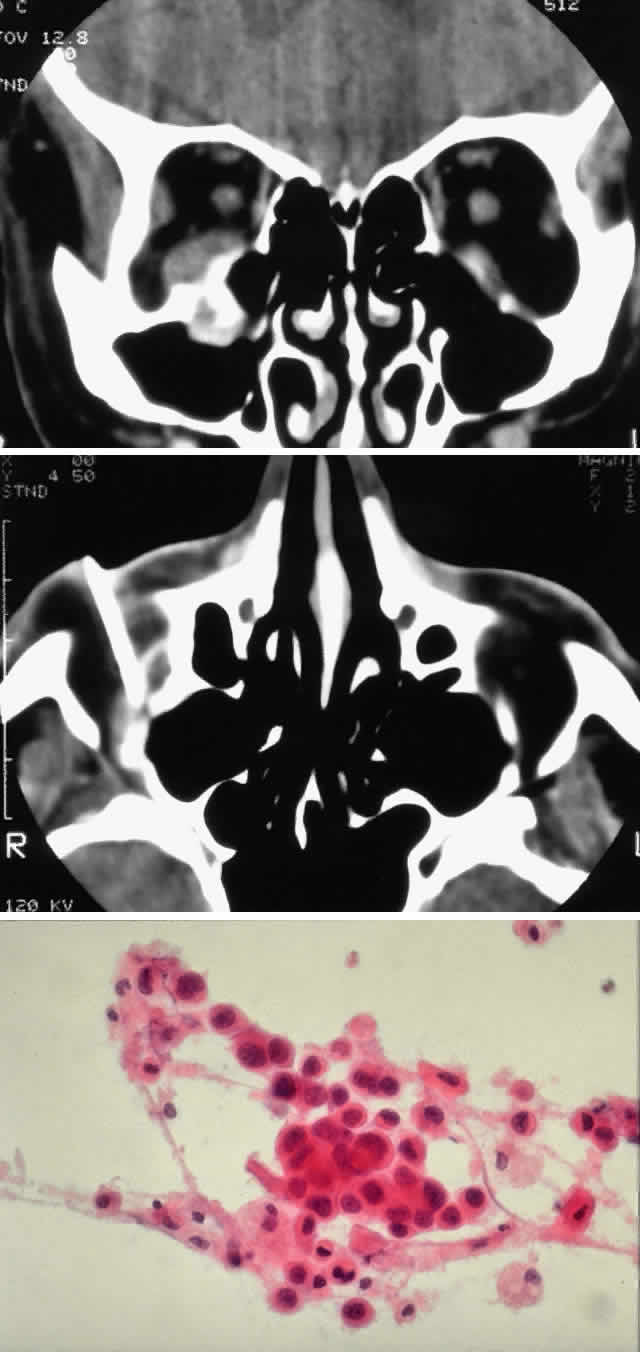

Fig. 4. A 36-year-old white woman presented with a 3-month history of progressive left proptosis associated with a retrobulbar pressure sensation. On external examination, she had bossing of the temporalis fossa and a proptosis of 9 mm axially, with a slight downward displacement of the globe. Ocular ductions were full, and there was no evidence of optic nerve compromise. CT scan on axial (A) and coronal (B) views confirmed a hyperostosing sphenoid wing meningioma with soft tissue components in the posterolateral orbit and anterior middle cranial fossa. During the next 20 months, her proptosis progressed to 11 mm, accompanied by increasing headaches and ocular pain, ocular restriction, and blurred vision in abduction. She underwent tumor resection with a combined frontotemporal orbitozygomatic approach, and she remains without evidence of recurrence 5 years after surgery. Visual function was preserved, and proptosis decreased to 2 mm.

Fig. 5. A 48-year-old Chinese woman had undergone previous frontotemporal craniotomy and partial excision of a left sphenoid wing meningioma. She presented 6 years later with progressive proptosis, visual loss, and numbness of the left cheek and upper teeth that developed during the preceding 2 years. On external examination, she had fullness of the temporalis fossa, an axial proptosis of 11 mm, and downward displacement of the left globe 2 mm (A). Ocular ductions were moderately restricted in all fields of gaze. She had no light perception, marked optic disc pallor, and an optociliary shunt vessel. CT scan revealed an extensive regrowth of meningioma involving the sphenoid wing, with soft tissue components in the temporalis and middle cranial fossae, parasellar region, and orbit, shown here on axial view (B). The lesion also involved the cavernous sinus and pterygopalatine fossa. She underwent a combined resection via the frontotemporal orbitozygomatic approach, followed by radiotherapy (50 Gy in 25 fractions over 5 weeks) for residual components in the cavernous and sphenoid sinuses. Two years after surgery, she remains comfortable and without radiographic evidence of tumor regrowth. Proptosis was reduced to 1 mm axially.